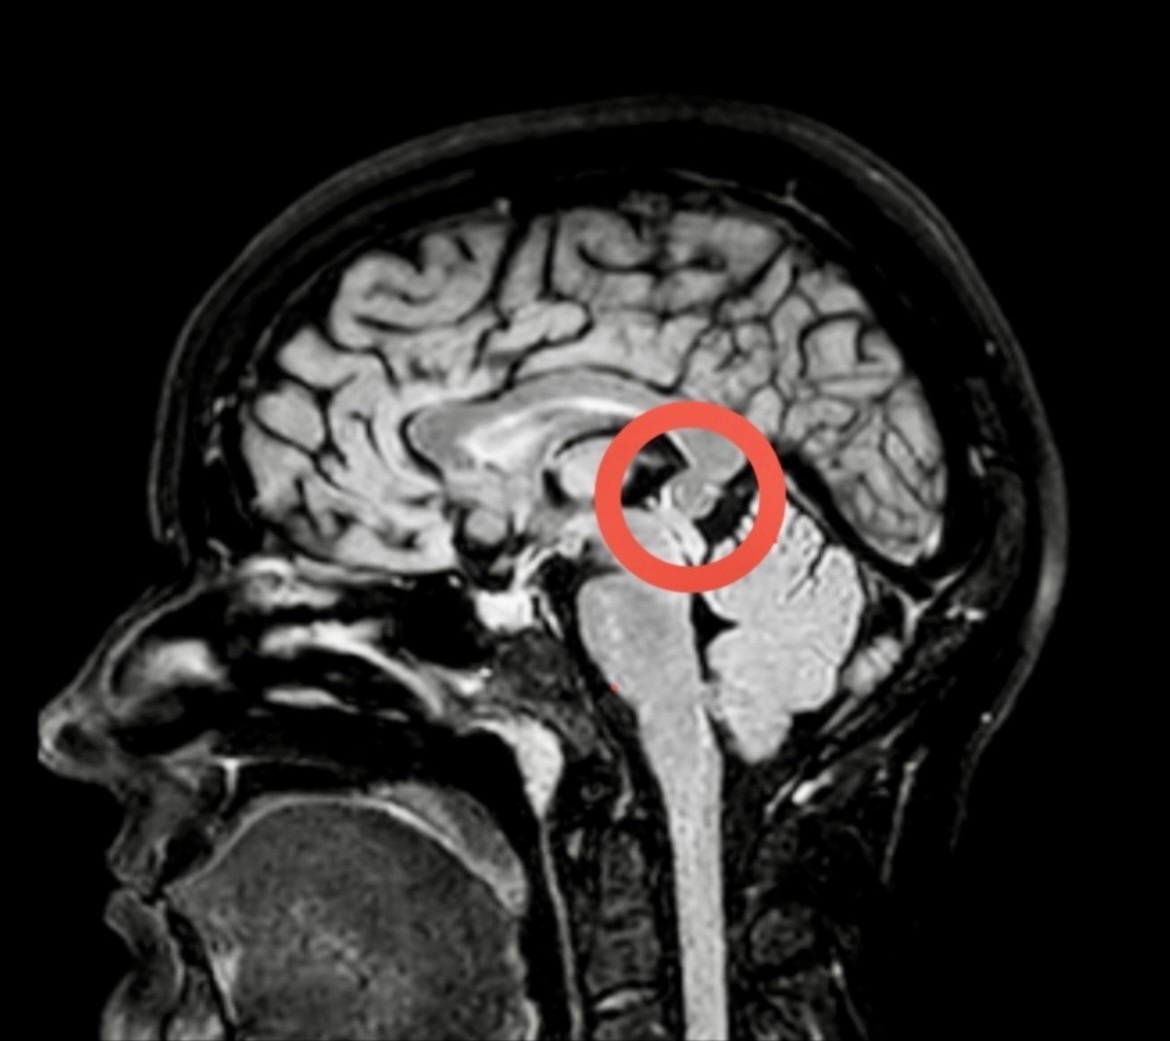

I’ve been diagnosed with a symptomatic pineal cyst — a brain tumour that, while benign, is pressing on vital structures, blocking cerebrospinal fluid flow, and causing severe daily symptoms including: migraine headaches, vision changes, balance issues, limb heaviness, neurological fatigue, and cognitive lapses that leave me exhausted, frightened, and unable to function as I used to.

Due to its size and location, I face worsening — and potentially permanent — cognitive damage and vision loss. My doctors believe I am already experiencing intermittent hydrocephalus, and without surgery I remain at risk of life‑threatening complications, such as an aneurysm.